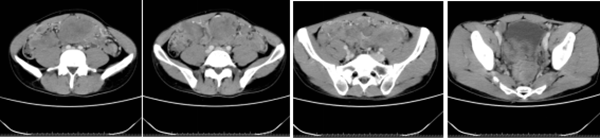

2020年3月,年仅32岁的小李第一次踏入湘雅常德医院肿瘤科门诊。小李给人的第一印象就是:身材消瘦,165cm的身高体重仅50kg,下腹部可以摸到5*6cm大小的活动性肿块。腹部CT可见腹腔内多发...